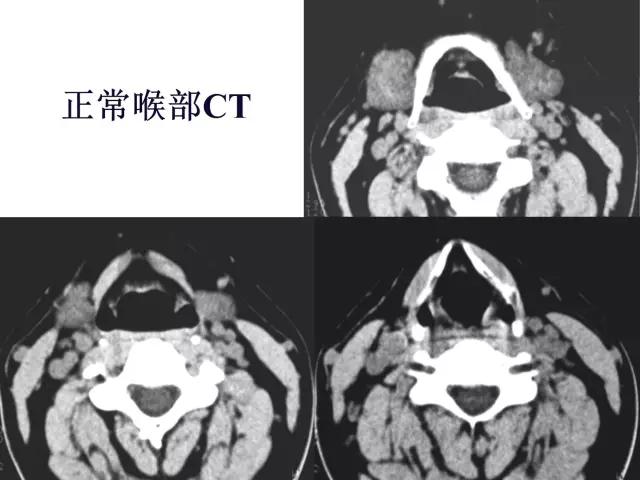

正常喉部CT

2、CT、MRI检查

2、CT

1、常规采用横断面扫描,喉腔中轴与扫描线垂直;

2、扫描范围自环状软骨下缘至下颌角会厌上缘,层厚3-5mm;

3、发音状态扫描:让病人连续发“E“音,这时声带内收,可较好显示声带、梨状窝、咽后壁及杓会厌壁的形态及病变。